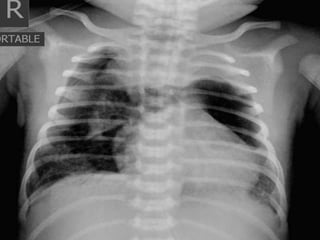

Bulging Fissure Sign

The bulging fissure sign refers to lobar consolidation where the affected

portion of the lung is expanded.

It is now rarely seen due to the widespread use of antibiotics.

Bulging Fissure Sign Thebulging fissure sign refers to lobar consolidation where the affected portion of the lung is expanded. It is now rarely seen due to the widespread use of antibiotics.